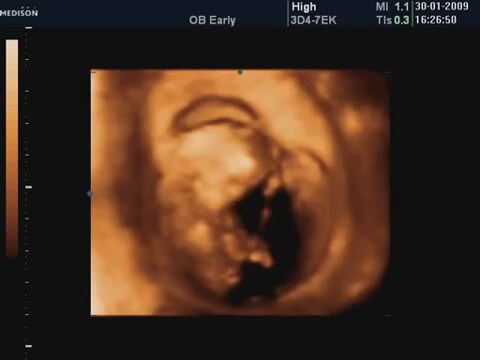

13 Haftalik Bebeğin 4 Boyutlu Ultrason Görüntüsü